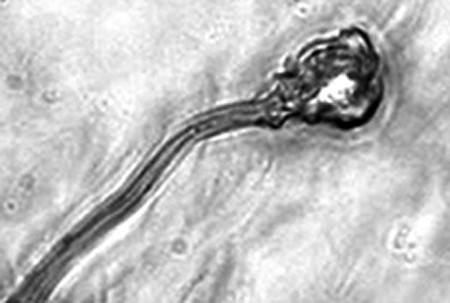

據報告的主要作者卡里姆教授介紹,這種試管培育精子(IVDsperm)與人類自然產生的精子并不完全一樣,但兩者擁有4個重要的相似點:它們包含有23個染色體;有精子那樣的頭和尾巴;有可以使卵細胞受精的蛋白質;它們也可以像天然精子一樣游動。